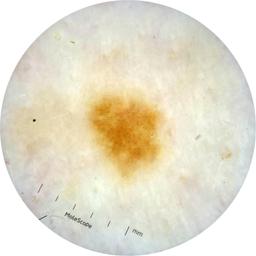

ISIC_9472333

Information

Dimensions

2057 x 2057

acquisition_day 230

age_approx 65

anatom_site_1 Trunk

anatom_site_2 Anterior trunk

anatom_site_general anterior torso

diagnosis_1 Benign

diagnosis_confirm_type single image expert consensus

image_type dermoscopic